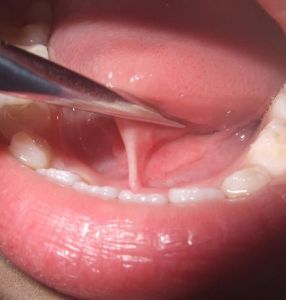

在舌的發育過程中,系帶逐漸向舌根部退縮。正常兒童2歲以後舌尖才逐漸遠離系帶。在少數發育不正常情況時才出現舌系帶過短。如果舌系帶一頭附著在舌尖,另一頭附著口腔底的前側,這樣就限制住舌頭的運動,向外不能伸出口外,向上又舔不到上齶,這就是舌系帶過短(俗稱“袢舌”)。

正常舌系帶可以使舌頭活動自如,但少數孩子的舌系帶發育不正常,可出現舌系帶過短(俗稱攀舌)的現象,臨床表現為舌頭不能正常自由地前伸,舌頭伸出口腔的部分不及正常兒童的長,而且舌前伸時舌尖因被舌筋牽拉而出現凹陷,舌尖呈W形(正常人舌頭伸出時舌尖呈V字形),還可能影響哺乳或與下前牙摩擦,發生潰瘍。孩子張口時舌尖不能上翹,不能舔到上齒齦或伸過上唇,年齡稍大後則影響正常發音。對於舌系帶過短的問題,不少家長存在以下幾個誤區。

舌系帶如果舌頭伸出口腔時舌尖出現一條溝而呈“M”形,或舌上卷時不能抵於齶部,則為舌帶過短。

如果餵奶時發現嬰兒吃奶裹不住奶頭而出現漏奶現象就應考慮有舌系帶過短的可能,但家長往往忽略了它;多數舌系帶過短的小兒是在接受體格檢查時被醫生偶然發現的。因此,當發現有以下情況應及時到醫院做進一步檢查:嬰兒吃奶裹不住奶頭而出現漏奶現象;讓孩子伸舌時,舌頭像被什麼東西牽住似的;舌頭伸出時舌尖呈“V”型凹入;舌系帶短而厚。